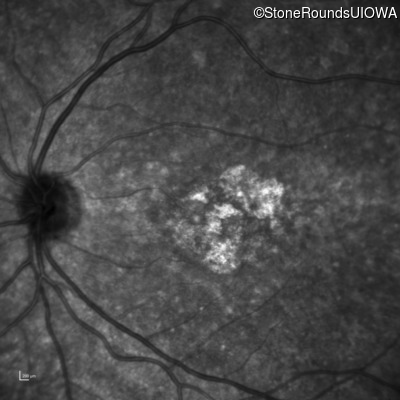

Age at visit: 26 years

OD OS

Age at visit: 27 years